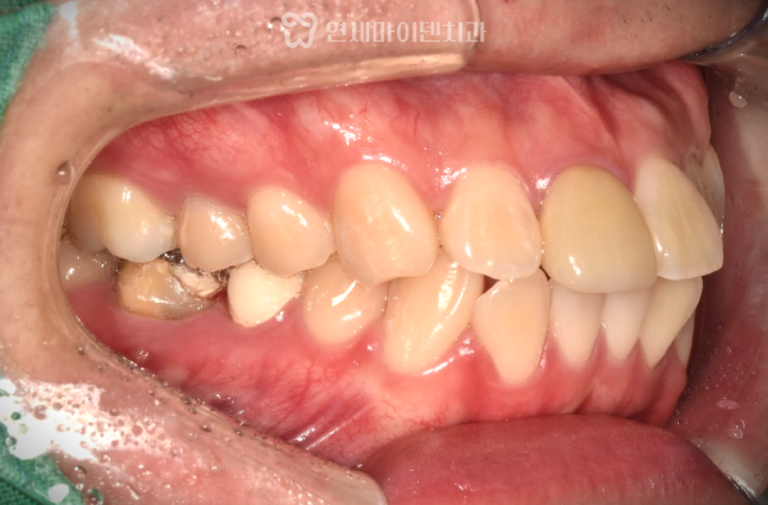

부분교정·임플란트 협진 증례: 쓰러진 어금니 “임플란트 해야 하는데치아가 쓰러져서 공간이 부족해요.” 임플란트를 계획하고 내원하신 분들 중의외로…